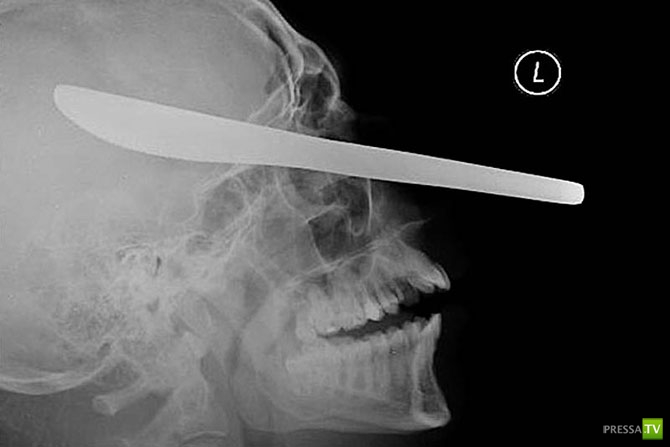

12-сантиметровый нож в черепе подростка.